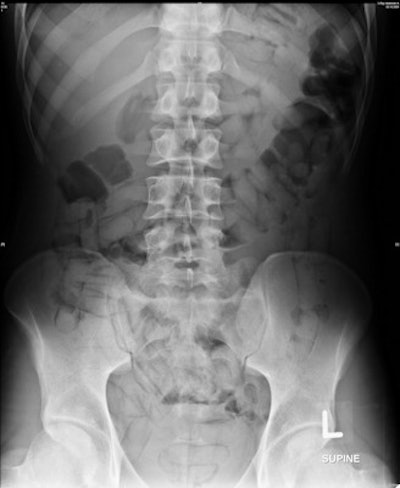

A case with a huge internal payload within the small and large bowel displaying the double condom sign and alignment of the packs representing the tic-tac sign. Radiological interpretation tends to under-report the total amount. In this case, the radiologists counted 45 to 66 concealed packs. The actual internal payload was 84 packs, collected from the feces as evidence.In terms of density, two (12.5%) of the 16 positively identified drug carriers were graded with an opacification of 3, meaning the packs were more opaque than the surrounding soft tissue. The remaining 14 (87.5%) cases were classified as 1 or 2 in equal numbers.